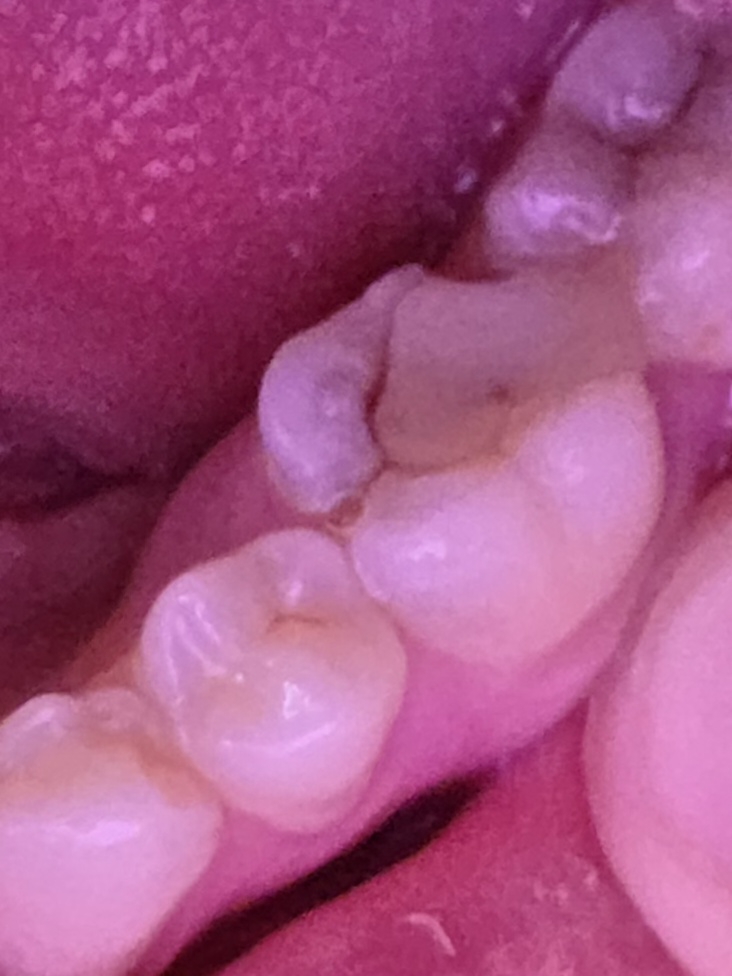

Аноним 11/03/26 Срд 10:00:50 1661799 271

>>1661798

Как повезет с корнями и верх\низ + навыки хирурга. Стоматолог-терапевт по совместительству палач мне низ драла около 1,5 часов раздрочив всю десну, второй снизу полу ретинированный хороший хирург распилила и удалила основную части минут за 25 и потом еще минут 15 выковыривала остатки корней и зашивала. Верхний за буквально 3 минуты она же удалила недавно.

Что положили наверно салфетка специальная, вроде бы есть саморассасывающиеся варианты, но это лучше уточнить что положили и нужно ли доставать через неделю и напомнить при повторном посещении. Заживление ускорить - соблюдай гигиену и рекомендации + питайся хорошо, в целом весь секрет. Для гигиены если низ то обычно ванночки из хлоргексина назначают + в зависимости от фантазии мажут метрогил дентой\асептой (через марлевую салфетку оставляя ее ненадолго чтобы слюна не смыла сразу.